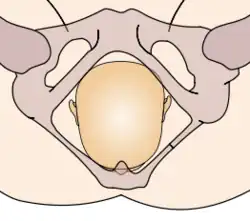

Durante la mecánica del parto, los diámetros menores del feto pasan por los diámetros mayores de la pelvis materna. Con el fin de no quedar encajado en algún punto durante su trayectoria fuera del útero, el neonato pasa por una serie de movimientos naturales que constituyen el mecanismo del parto.

- Descenso: ocurre por acción de la gravedad una vez dilatado el cuello uterino, así como de las poderosas contracciones uterinas y de los músculos abdominales maternos. El descenso tiende a ser lentamente progresivo basado en la estructura pélvica materna.

- Flexión: la cabeza del feto se flexiona, de modo que el mentón fetal hace contacto con su pecho, al encontrarse el primer punto de resistencia del piso pélvico.

- Encajamiento: el diámetro de la cabeza del feto que va desde un hueso parietal al opuesto, llamado diámetro biparietal, alcanza el estrecho superior de la pelvis a nivel de las espinas isquiáticas. Por lo general ocurre en la fase tardía del embarazo, justo al iniciarse el trabajo de parto.

- Rotación interna: ocurre en el estrecho medio de la pelvis, cuando el feto, al continuar su descenso, hace una rotación de 90° en el sentido contrario a las agujas del reloj, de modo de adaptarse a la configuración romboidal de los músculos del piso pélvico, entre el músculo elevador del ano y los ileocoxígeos. Así, la cara del bebé está dirigida mirando hacia el recto materno.

- Extensión: la cabeza del feto atraviesa el canal del parto, se extiende de tal manera que la frente se desplaza primero por el orificio vulvar. La cabeza está por debajo de la sínfisis púbica y ha distendido al máximo el perineo.

- Rotación externa: una vez que ha salido la cabeza, se gira 45° para restaurar su posición original antes de la rotación interna y quedar en posición normal en relación con los hombros. Se denomina por ella la restitución, haciendo el paso de los hombros más factible.

- Expulsión: el hombro púbico tiende a salir primero, seguido por el hombro perineal. El resto del cuerpo sale por sí solo con una leve impulsión materna.

Estos movimientos son todos debido a la relación que existe entre la cabeza ósea y hombros del feto y el anillo óseo de la pelvis materna.

La relación de la fontanela posterior con la pelvis materna determina el diagnóstico de posición. Se distinguen ocho posiciones en la presentación de vértice: I. Occípito ilíaca izquierda anterior (OIIA) en que la fontanela posterior se ubica hacia delante en relación con la pelvis materna y además a la izquierda de la madre. La sutura sagital está orientada oblicuamente. II. Sucesivamente dependiendo de la ubicación de la fontanela posterior (porque la pelvis es siempre la misma) las posiciones serán: